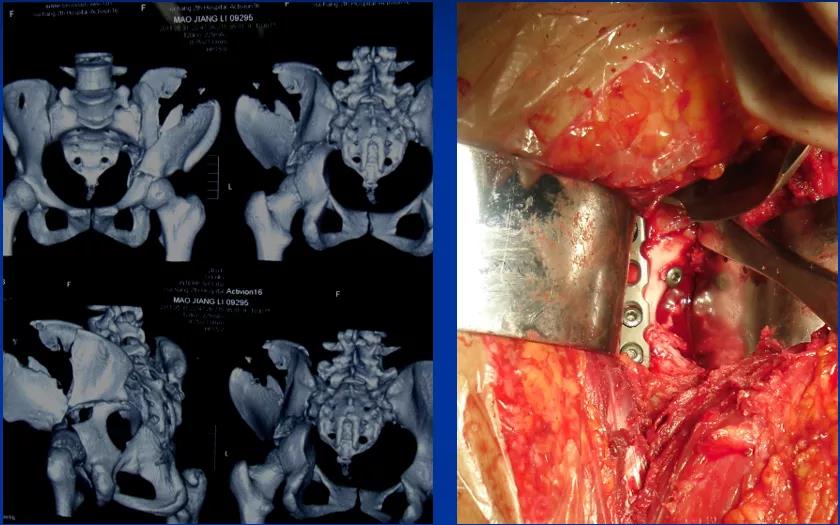

——典型案例——

微创插板病历后路有限切开,结合前路微创插板内

——髋臼骨折CT检查重要性——

1、显示常规X线不能显示的骨折,有助于诊断;2、可以清楚的显示关节内的碎骨块;3、显示关节面压缩、程度;4、精确显示骨折移位程度;5、定量显示后壁缺损情况;6、有助于术后分析。